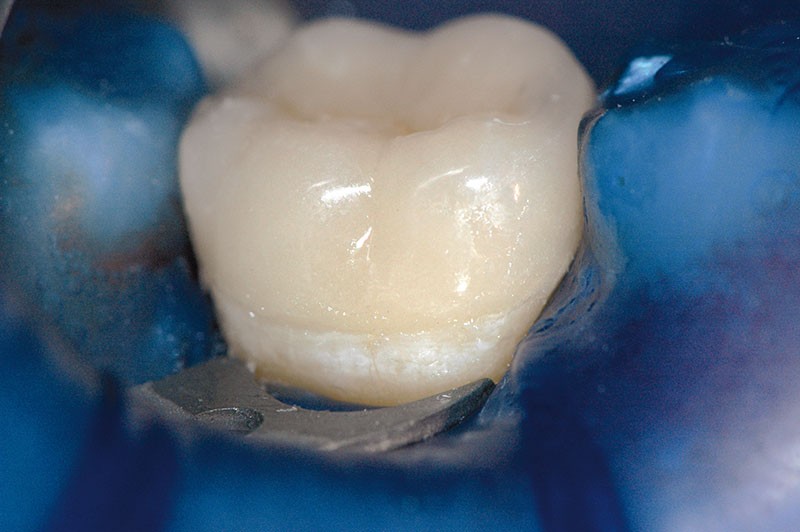

Dans ces situations, le praticien est conduit à dépulper et à restaurer les dents traitées endodontiquement. Les traitements doivent alors s’inscrire dans le concept du continuum endo-restaurateur qui a été défini comme étant « le processus spatio-temporel sans interruption ni rupture qui débute par l’accès à l’endodonte et s’achève avec la mise en place de la restauration prothétique d’usage » (1). Il existe bien une continuité, du traitement endodontique à la restauration fonctionnelle d’usage qui conditionne le pronostic et les résultats du traitement à long terme (fig. 2).